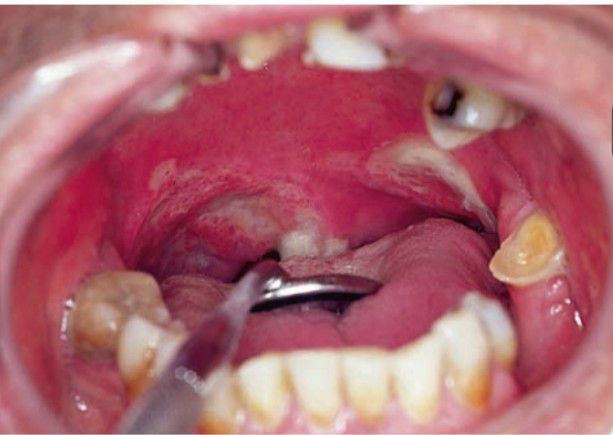

Midline granuloma as oropharyngeal ulcer

Midline granuloma/extranodal NK/T-cell lymphoma is a unifocal destructive and aggressive process, generally in the midline of the oronasal region